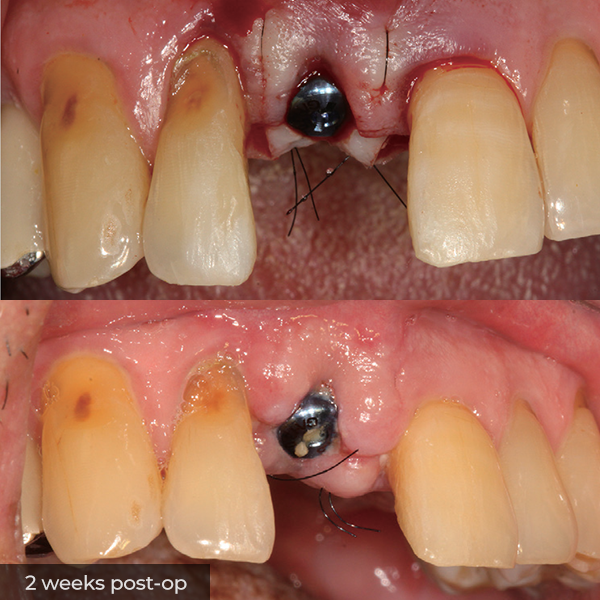

Director’s Clinical Cases

Director’s Clinical Cases